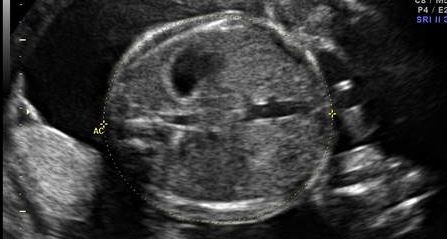

As medidas do tórax e abdome fetal permitem avaliar o crescimento visceral e identificar alterações como restrição de crescimento, macrossomia e malformações renais. A circunferência abdominal (CA) é um dos parâmetros mais utilizados na estimativa de peso fetal.

Circunferência Abdominal e Torácica

CA e CT · 12 a 40 semanas